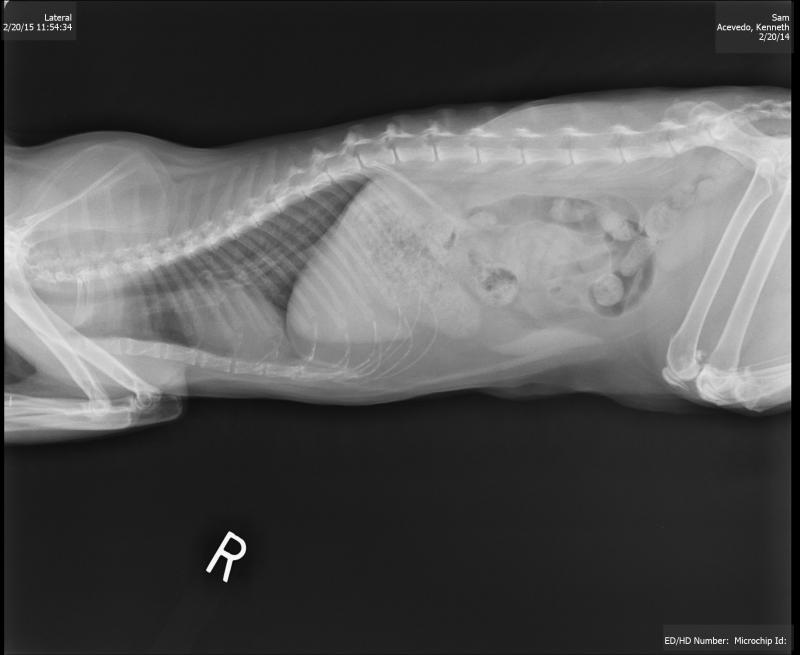

DIAGNOSTICS

Radiographic view canine patient...abdominal.

Dr. Brown performs an ultrasound as part of a diagnostic office visit to determine what internal problems may exist causing this cat to have urinary incontinence and difficulty.